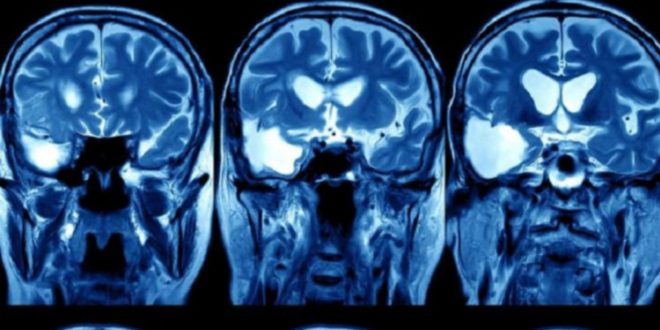

يعتزم مستشفى بريطاني استخدام نظام الذكاء الصناعي لغوغل، المعروف باسم “ديب مايند”، لتحليل صور الأشعة المقطعية وأشعة الرنين المغناطيسي لـ 700 مريض سابق في وحدة العلاج الإشعاعي لمرضى السرطان .